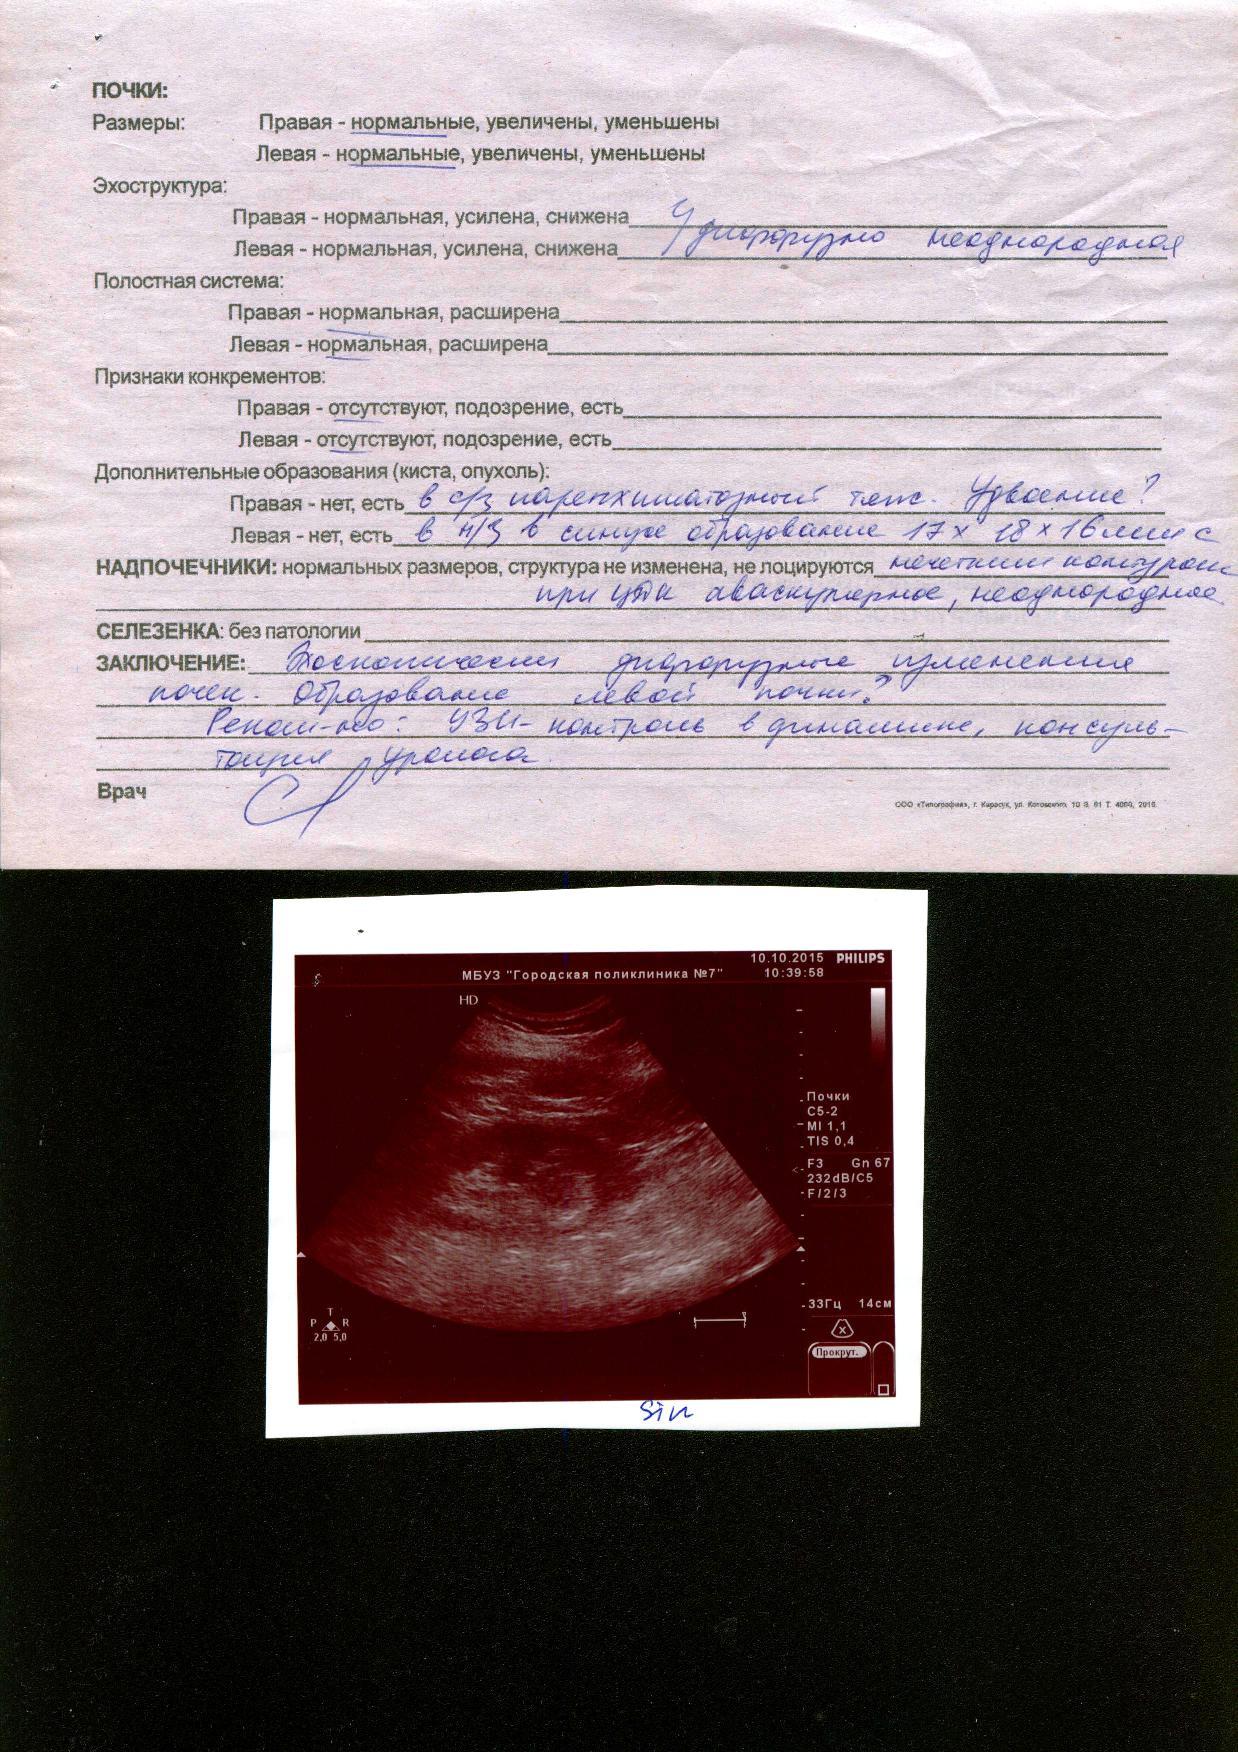

Консультация по результатам УЗИ почек

10 октября 2015 - 16:54

Мужской

84 года

Прошу Вас посмотреть моё УЗИ почек и дать рекомендации по лечению.

Ответ врача

Шадёркин Игорь Аркадьевич

К сожалению, увеличение недостаточно для восприятия текста. Напечатайте текст в письме, но дословно.